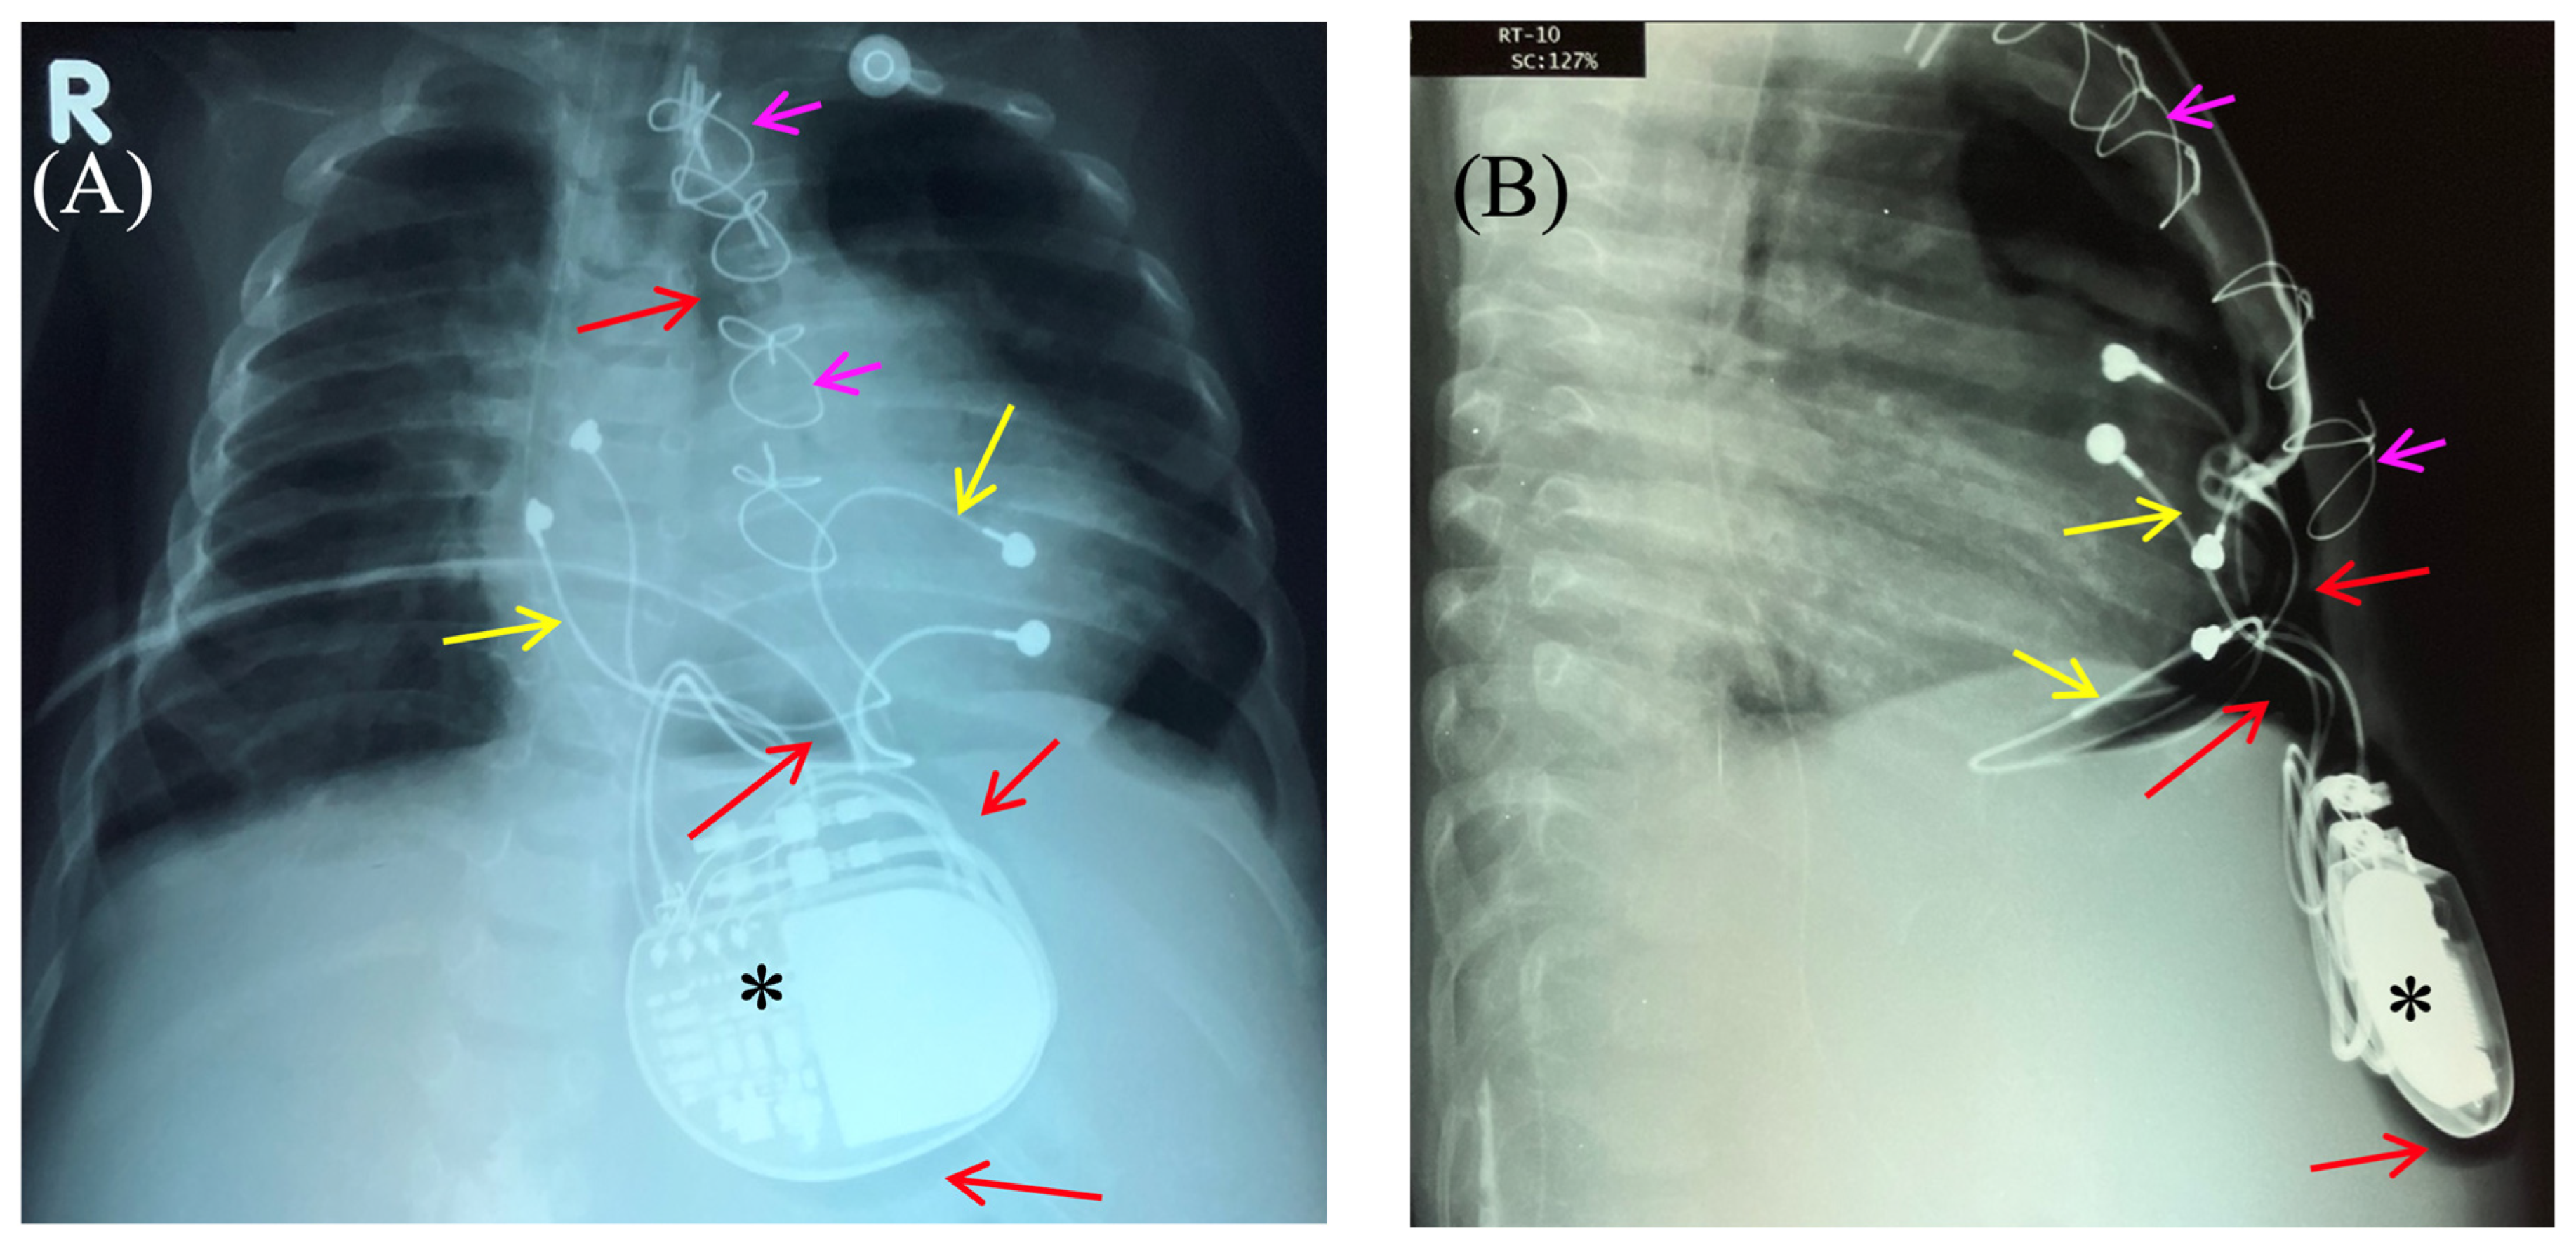

Fluoroscopy and chest and abdominal radiography revealed no signs of pneumothorax. A demarcated area of free air was visualized in the upper anterior abdominal wall along the midline, projecting to the pacemaker pocket. The passage of radiocontrast agent through the gastrointestinal tract was observed dynamically and found to be normal. No signs of hollow organ perforation or intestinal obstruction were detected (Figure 2, Figure 3 and Figure 4).

Figure 2. Chest X-ray—frontal (A) and lateral (B) view. Chest X-ray shows no pneumothorax, but pneumopericardium, pneumomediastinum and air in the pacemaker pocket site (red arrow) are present. One can also see the pacemaker electrodes (yellow arrow), the pulse generator (black asterisk), and the wire ligature (pink arrow). R: right side.